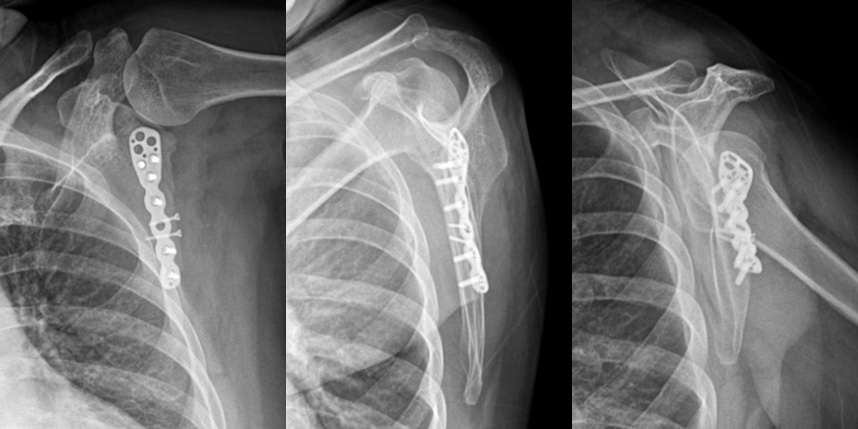

상완골 골절